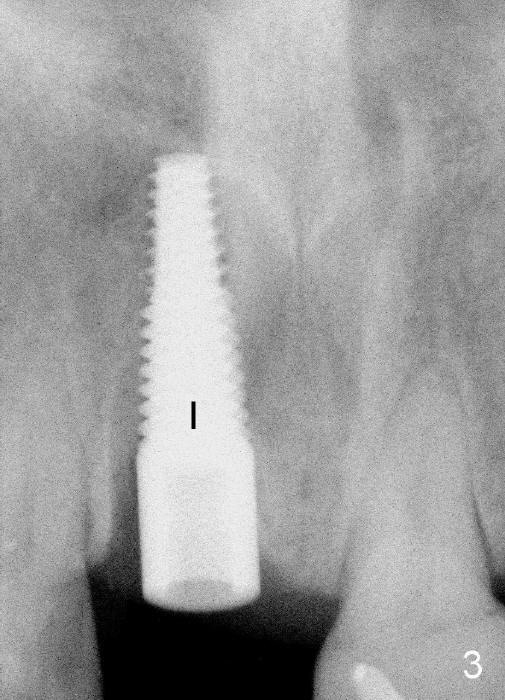

其实临床情况千变万化,处理方法可以有所变化。朱女士六十来岁,后牙缺失严重,右上中切牙根管治疗重做后感染复发(图一*:根尖阴影),但是没有任何症状,不久牙冠脱落,根尖瘘道(图二箭头)。估计炎症不是那么严重,拔牙后,常规牙槽窝处理,开始即刻植牙。处理颊侧根尖缺失办法,不是植骨,理由是植骨和植牙同时进行,增加身体负担,它们都是异物。

植牙窝适当远离颊侧根尖缺失处,植牙过程可能自行缩小,关闭缺失,最后身体自然修复。